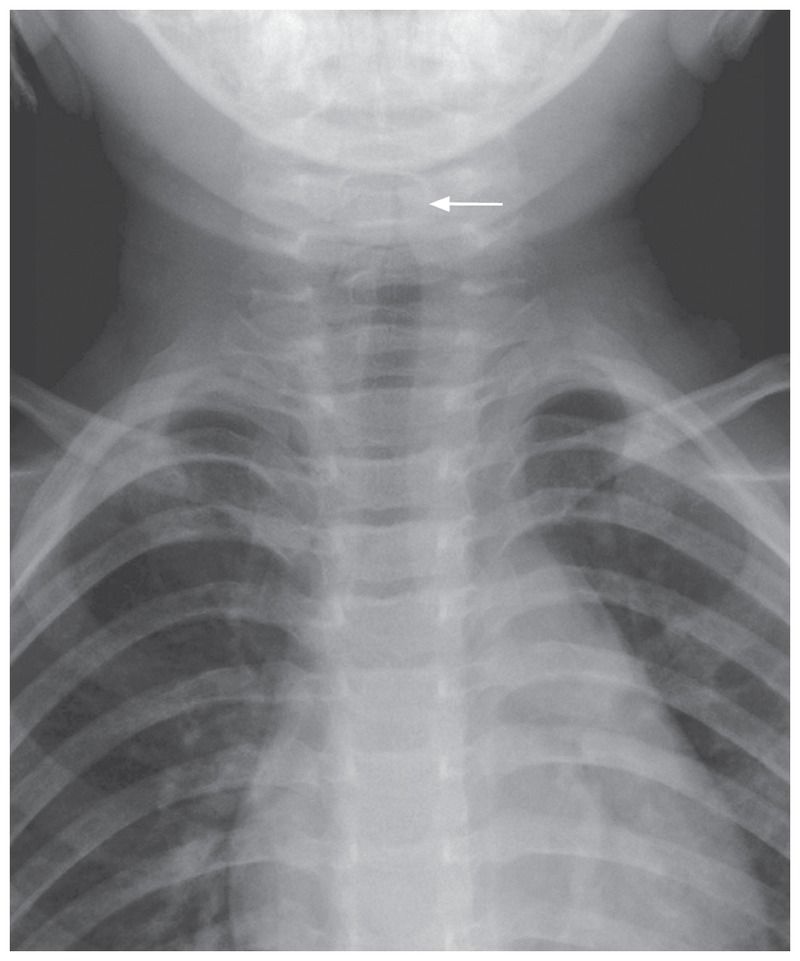

An oropharyngeal examination did not detect any major abnormality. Chest radiography showed a so-called steeple sign, which results from subglottic narrowing of the trachea (arrow) and is suggestive of the diagnosis of laryngotracheobronchitis, or croup.